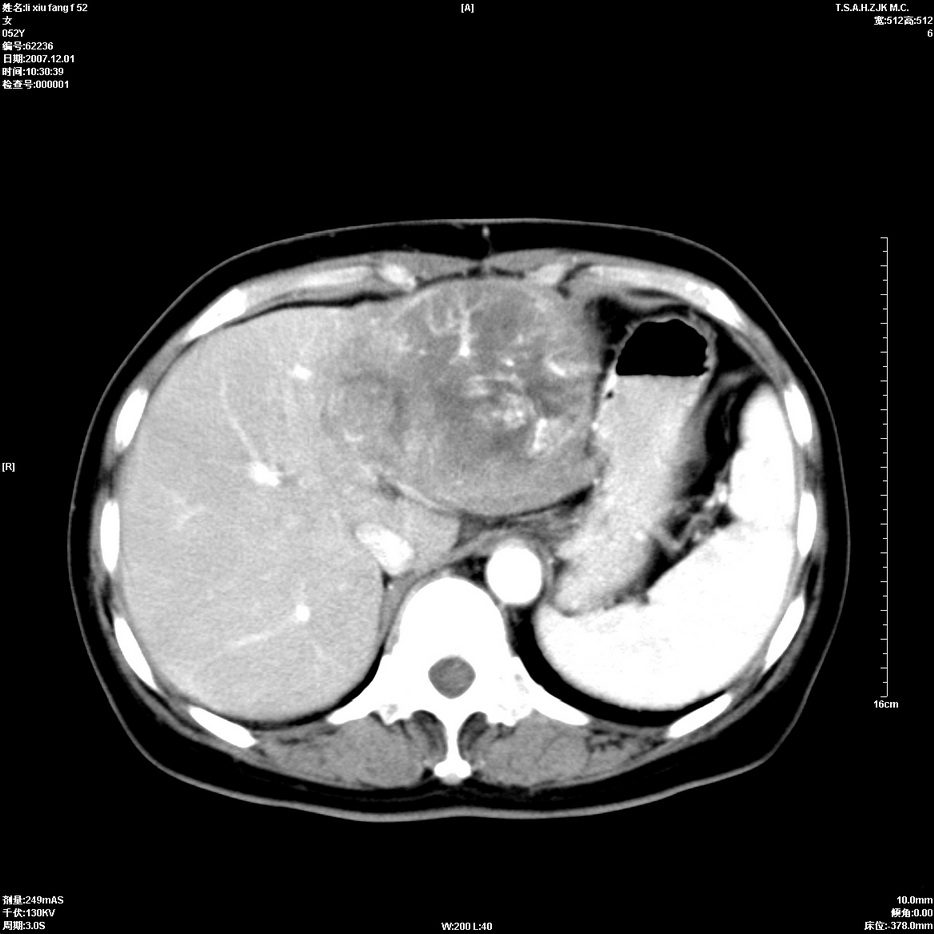

标题: CT12858:女,52岁,胎甲球蛋白861肝左叶占位,肝癌。下腔静 [打印本页]

标题: CT12858:女,52岁,胎甲球蛋白861肝左叶占位,肝癌。下腔静

肝左叶巨大低密度灶肿块,增强符合快进快出表现,有动静脉交通支;静脉期,下腔静脉内有充盈缺损,afp明显升高,支持肝癌并下腔静脉癌栓形成。

支持楼主   门静脉主干及左支癌栓形成

以下是引用拾荒者在2008-4-15 22:57:00的发言:[br]肝左叶巨大低密度灶肿块,增强符合快进快出表现,有动静脉交通支;静脉期,下腔静脉内有充盈缺损,afp明显升高,支持肝癌并下腔静脉癌栓形成。